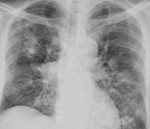

• Радиационная диагностика. При одиночном отростке на рентгенограмме легких визуализируются плотные округлые очаги. При диффузных поражениях дыхательных путей бронхолегочный рисунок улучшается, выявляется небольшое очаговое распространение. На плевральный амилоидоз указывают признаки гидроторакса - плотное затенение с косой линией Дамуасо в нижних отделах легких. КТ легких также выявляет увеличение средостенных лимфатических узлов.